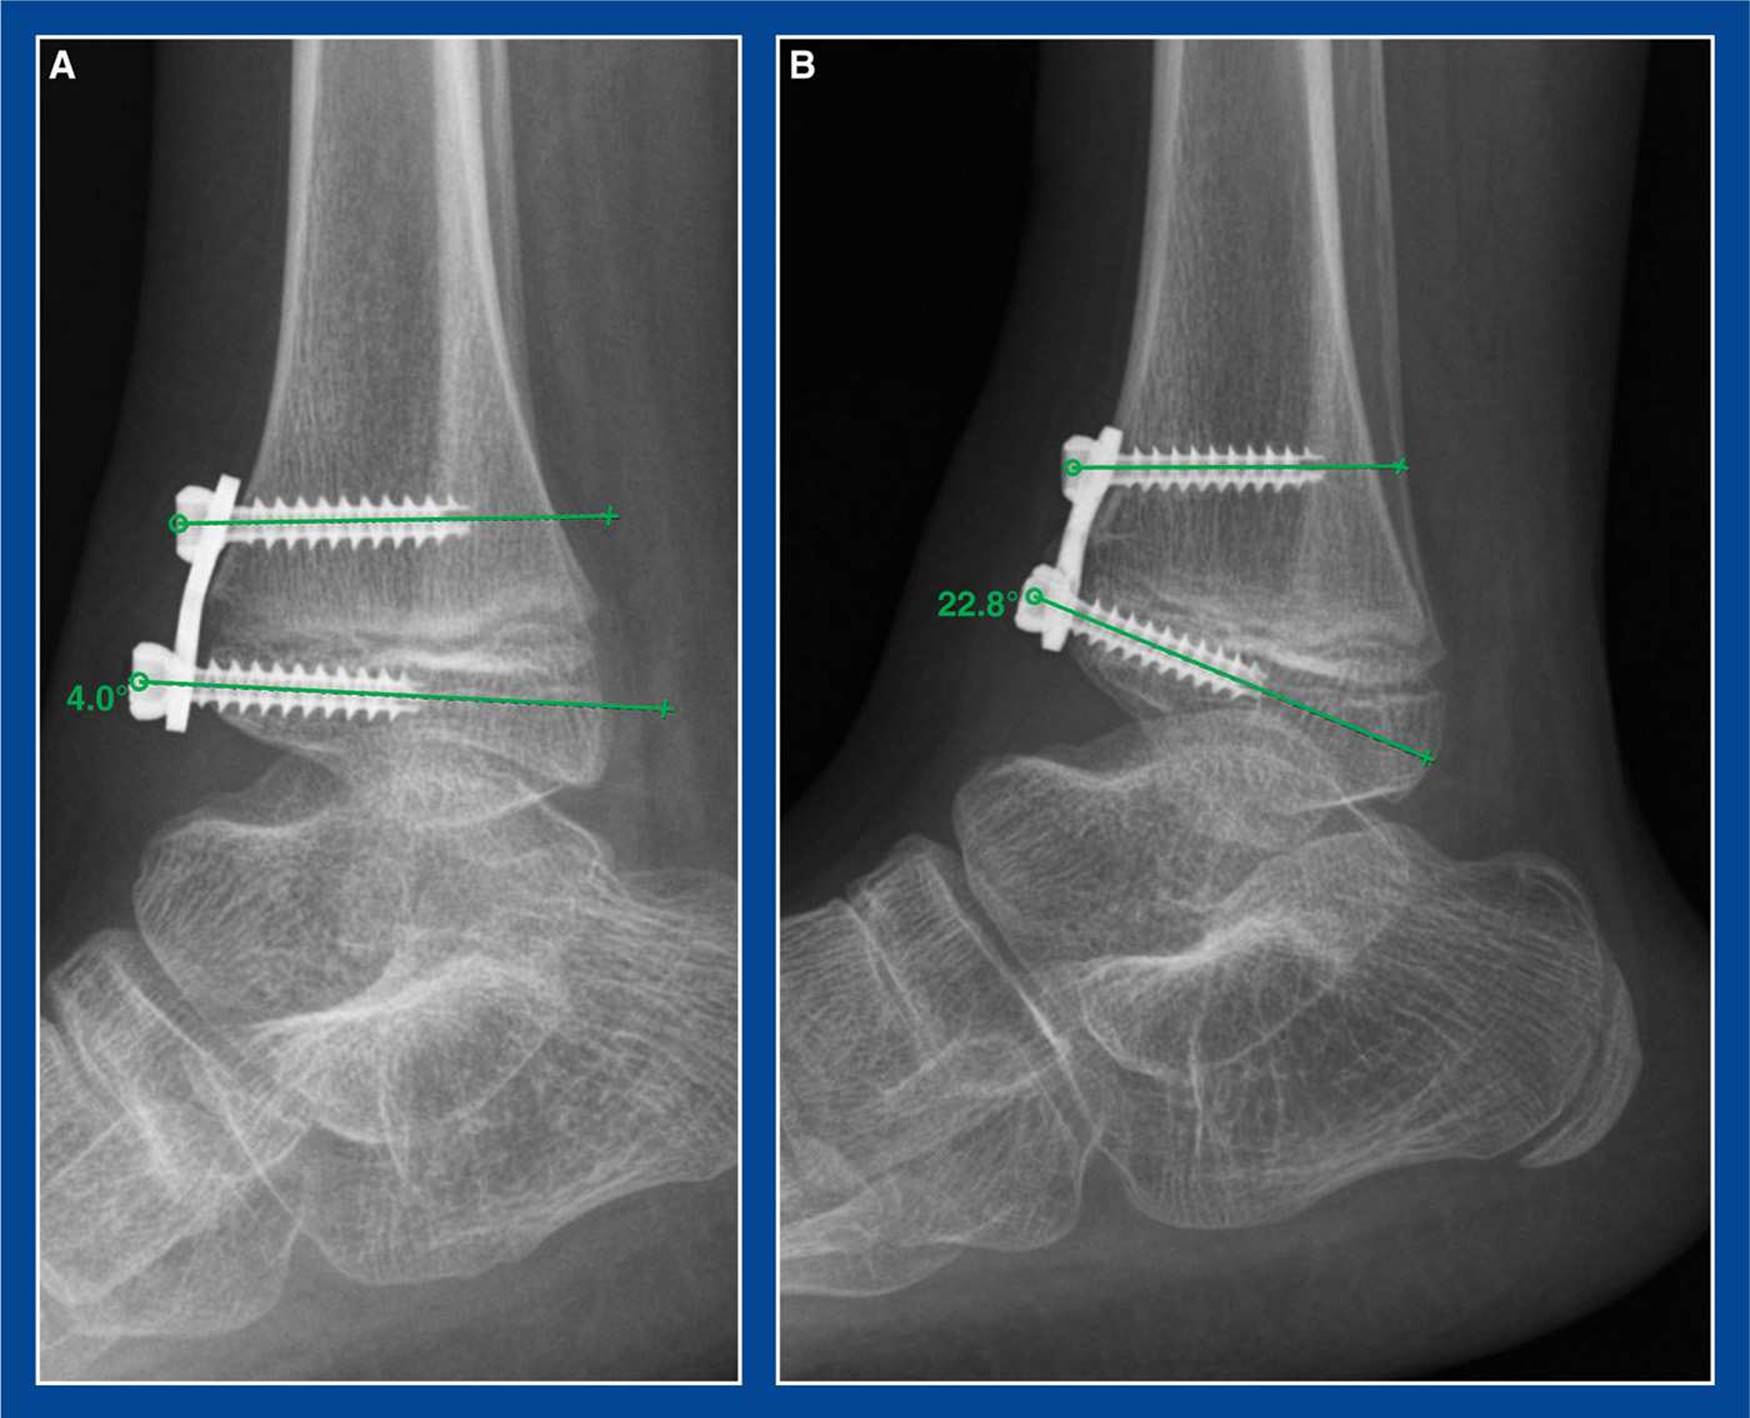

Figure 8-2. Guided growth for anterior ankle impingement. A. Plate/screw construct is seen bridging the anterior distal tibial physis. B. Several months later, the joint has reoriented and grown into recurvatum, thereby increasing dorsiflexion and decreasing the painful anterior ankle impingement.